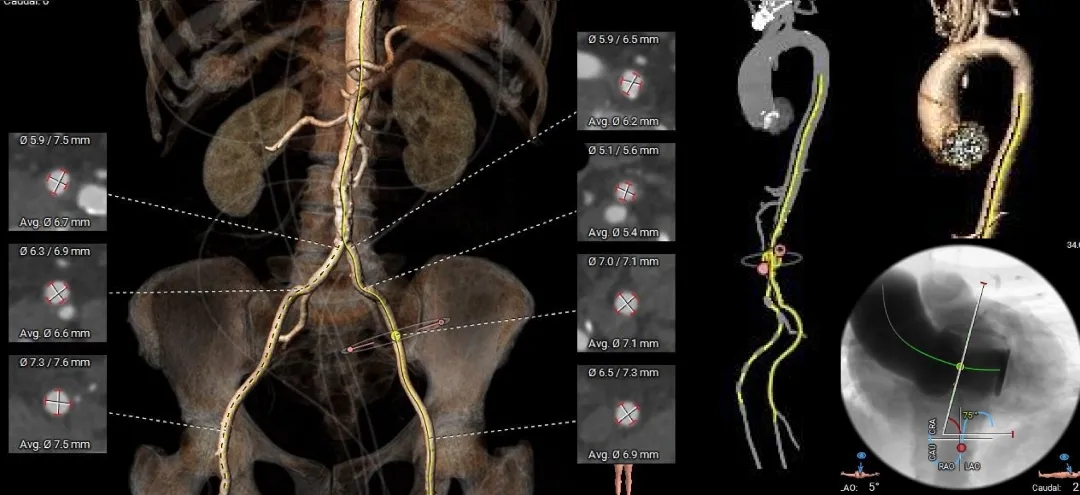

Case Ⅰ

TYPE1型二叶瓣重度狭窄,L-R融合,75°横位心,伴中重度钙化TAVR

术前CT分析

TYPE-1L-R融合二叶瓣,中-重度钙化,流出道收口型,升主动脉未见扩张;

双侧冠脉高度可,冠脉阻挡风险不高;

瓣环水平夹角75°,横位心;

外周血管内径充足,双侧髂动脉及腹主动脉可见明显钙化,无明显迂曲;

根据瓣环及瓣上结构选择 ScienCrown TF25mm瓣膜。

主动脉根部测量

Annulus

22.8mm

LVOT

20.4mm

钙化积分:

665mm3

SOV:

33.1*35*34.3mm

STJ:

34.5mm

AAO:

41.2mm

瓣上结构测量

瓣上2mm

23.6mm

瓣上4mm

23.8mm

瓣上6mm

22.5mm

瓣上8mm

冠脉风险评估

外周入路评估